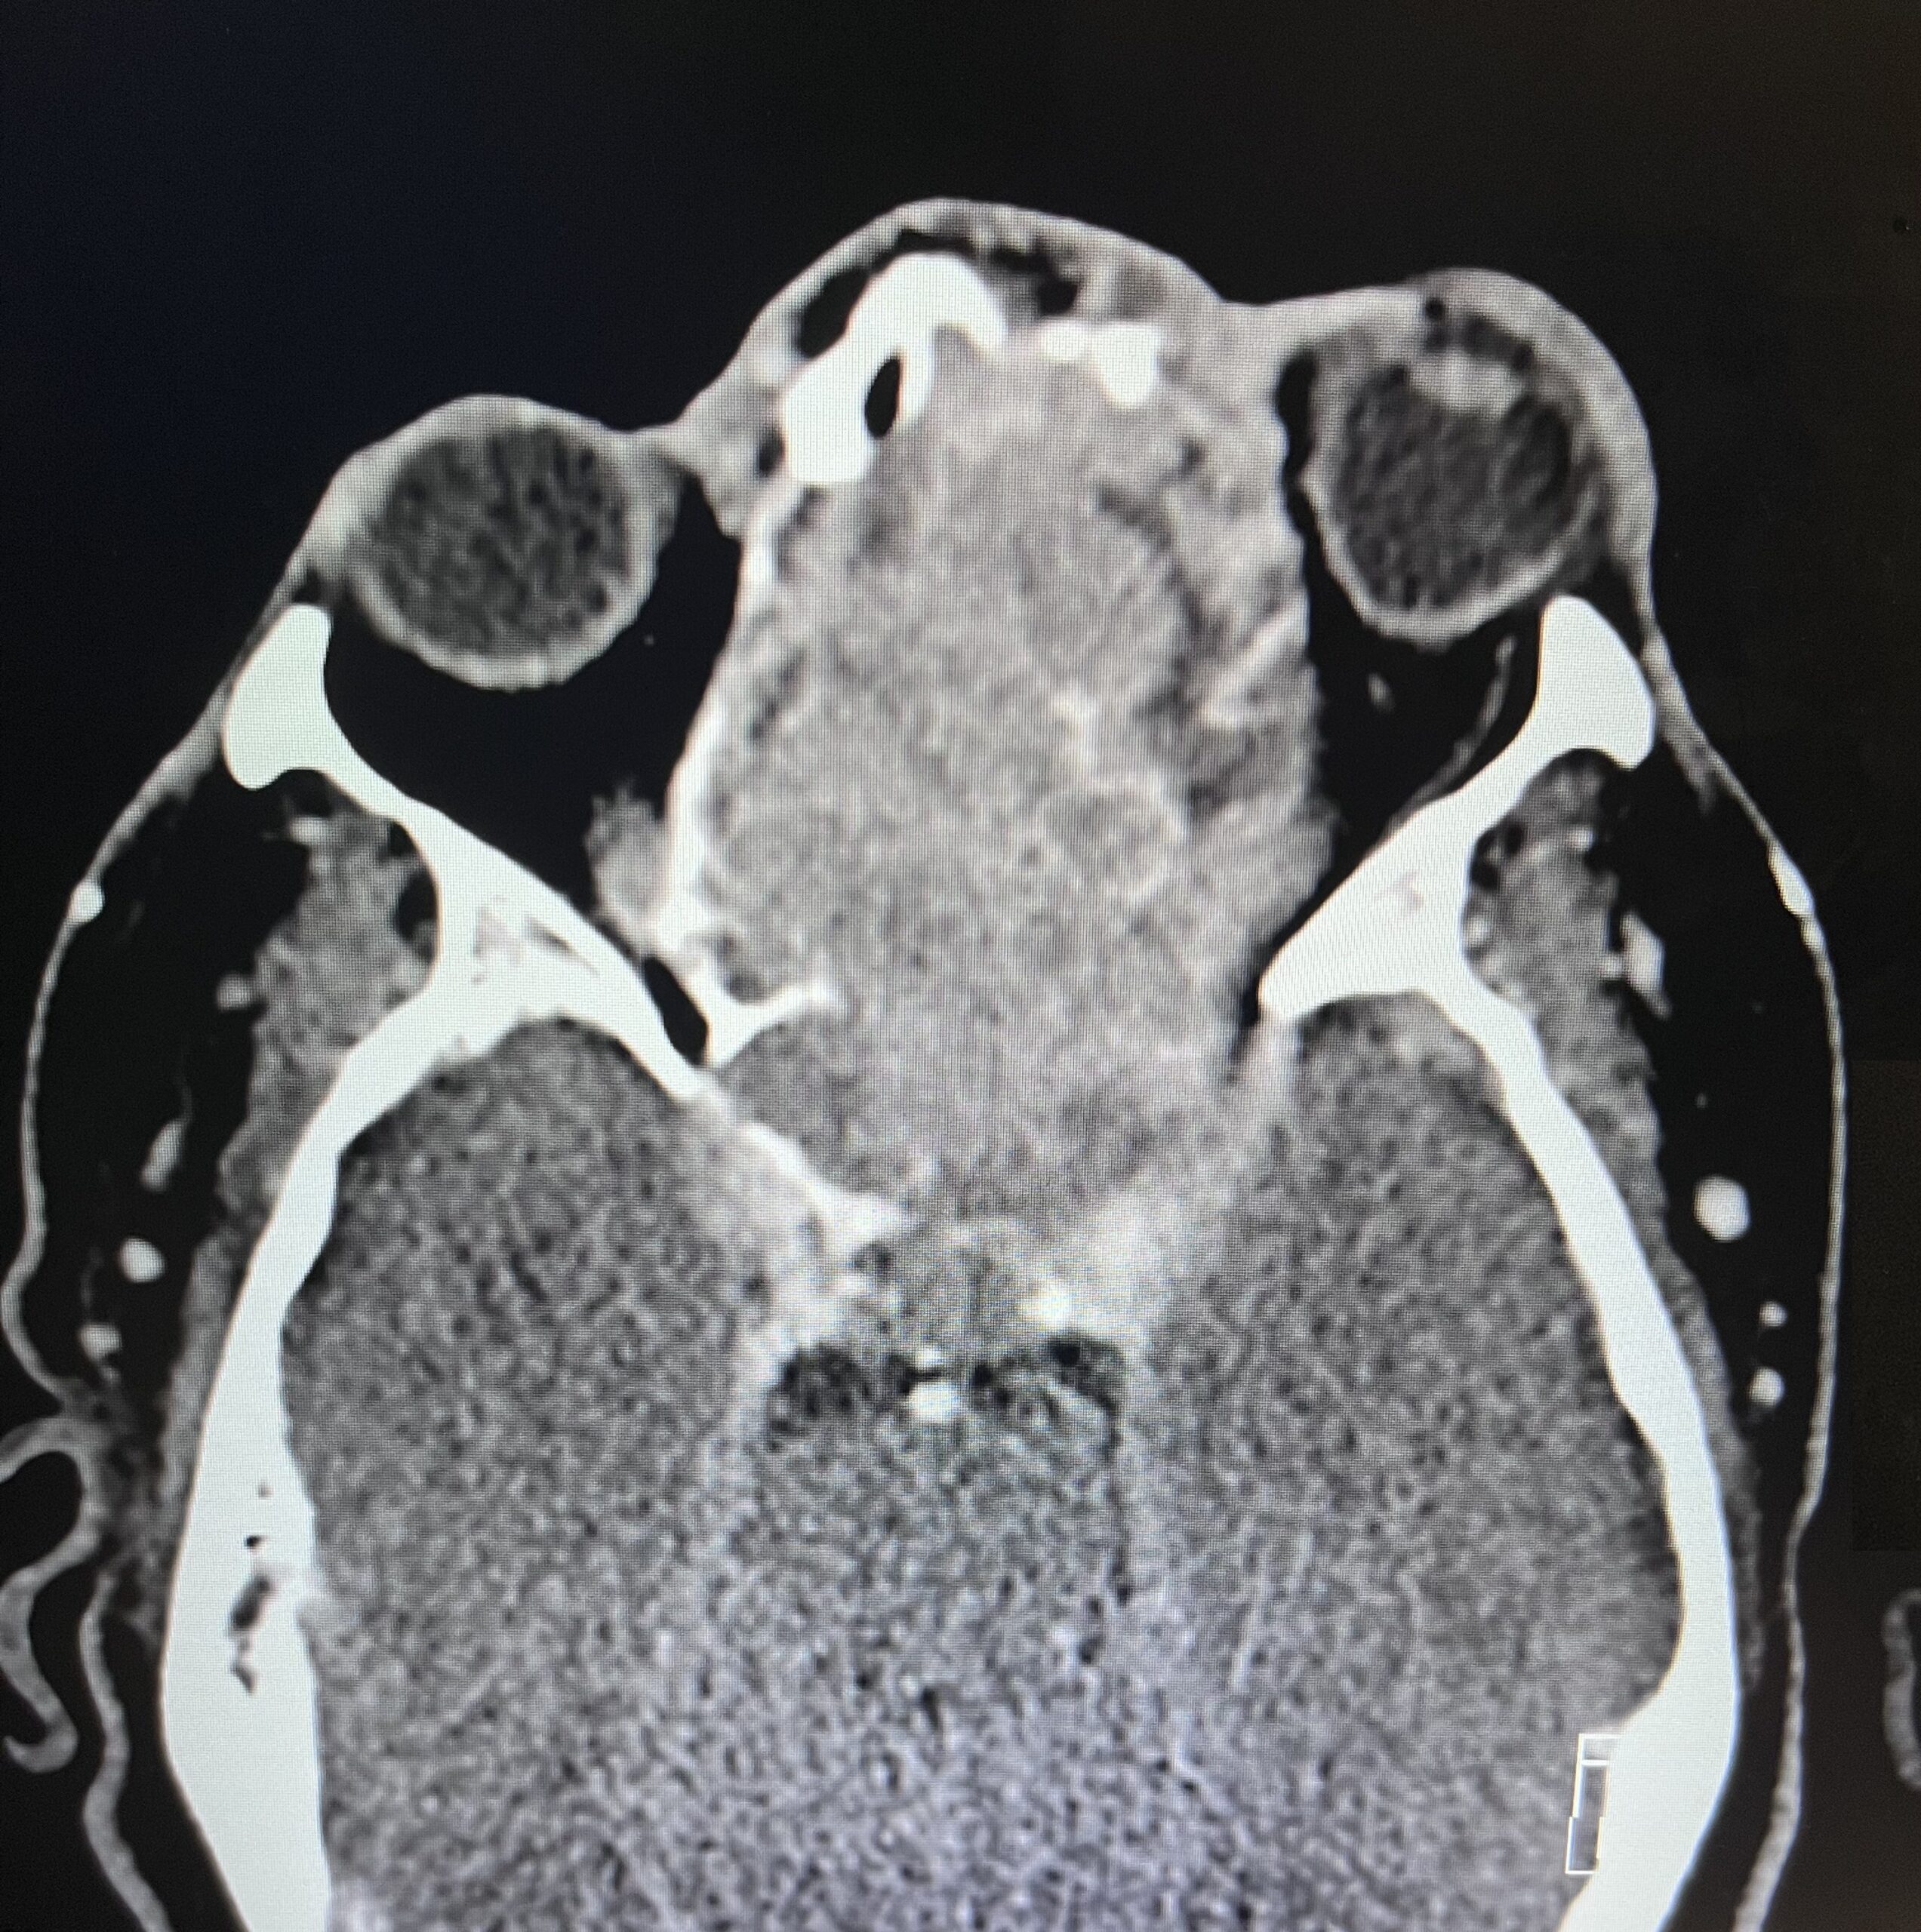

Sinonasal carcinoma is a rare malignancy that often presents with nonspecific symptoms, making early diagnosis challenging. Delayed recognition can lead to disease progression and worse outcomes. This case report emphasizes the importance of early identification, prompt imaging, and multidisciplinary management. A 73-year-old male with a history of anemia and hypertension presented with progressive facial swelling, 20-pound weight loss, and vision loss in the left eye over two months. Initially misdiagnosed with bacterial sinusitis, his symptoms persisted. Examination revealed a proptotic left eye and a large obstructive nasal mass. Computed tomography (CT) and MRI (magnetic resonance imaging) demonstrated a destructive sinonasal mass with skull base and intracranial extension. A biopsy confirmed sinonasal carcinoma, and the patient was started on chemoradiation therapy due to the inoperability of the tumor.

This case underscores the importance of recognizing red flag symptoms such as persistent facial swelling and neurological deficits. Multimodal imaging played a critical role in diagnosis. The literature suggests sinonasal carcinoma is often diagnosed late, reinforcing the need for early suspicion and specialist referral. Sinonasal carcinoma should be considered in patients with persistent facial or nasal symptoms. Timely imaging, biopsy, and interdisciplinary care are essential for optimizing outcomes.